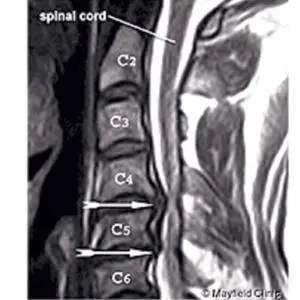

Terjadi ketika bantalan sendi atau diskus di antara ruas tulang belakang bagian leher menipis dan gel di dalamnya menonjol keluar mengenai saraf yang ada di dekatnya.

Beberapa tes lanjutan akan dilakukan untuk membantu menetapkan diagnosis sakit leher, di antaranya: Foto Rontgen, CT scan, dan MRI untuk melihat struktur tulang, otot dan saraf serta sendi, elektromiografi (EMG) untuk mengetahui fungsi saraf. Pemeriksaan darah berfungsi untuk mencari infeksi virus atau bakteri.